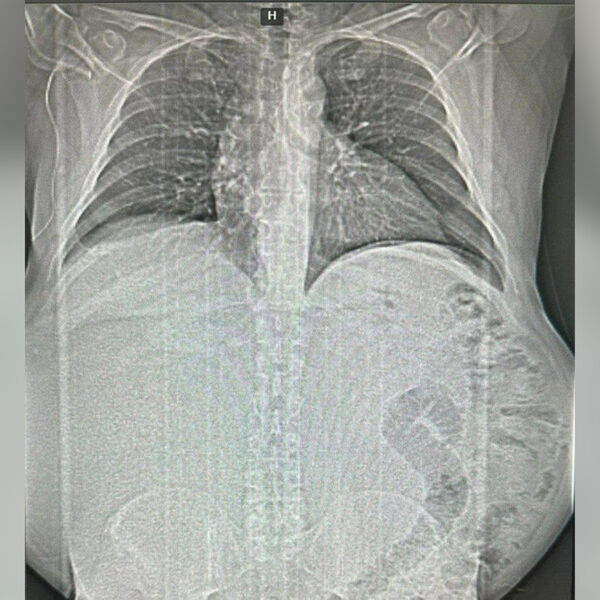

Россиянин не обращался к врачам и вырастил 17-килограммовую опухоль

В Краснодаре спасли мужчину с 17-килограммовой опухолью в животе

Врачи Краевой rлинической больницы №1 имени профессора С.В. Очаповского спасли пациента, удалив ему гигантскую опухоль. Об этом министр здравоохранения Краснодарского края Евгений Филиппов сообщил в своем Telegram-канале.

Как рассказал глава ведомства, пациент активно болел около года — он стремительно набирал вес, но не обращался за помощью, так как развивавшееся образование не мешало жить. Во время диагностики медики нашли у пациента объемное новообразование в брюшной полости.

Операция по удалению новообразования длилась четыре часа. Вес опухоли составил около 17 килограммов.